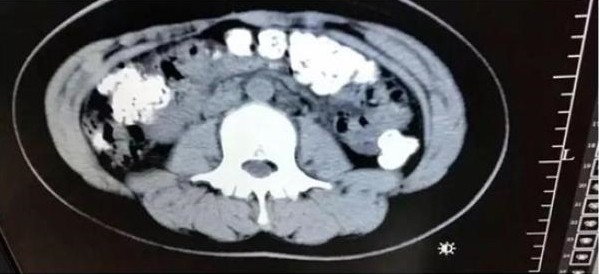

▼根據中國《澎湃新聞》的報導,這名14歲少女於5月28日在父母陪同下來到浙江諸暨市人民醫院急診。原來她已經連續5天都腹痛不已,不僅沒有排便更吃不下東西,當時醫師見她肚子鼓鼓的,於是安排了她做腹部 CT,結果發現患者的胃部、橫結腸、升結腸、降結腸、乙狀結腸一直到肛門,都佈滿了密密麻麻的顆粒陰影!

▼醫師馬上追問少女最近吃了什麼不易消化的食物,少女才支支吾吾的表示,自己5天前喝了珍珠奶茶。不過醫師推斷少女體內未消化珍珠的數量不像是喝一杯珍奶就能累積的,應該是近期都有喝了一段時間,因為害怕父母念她才會選擇隱瞞。最後醫師開了一些「潤腸通便」的藥物,協助她把未消化的「珍珠」排出體外。